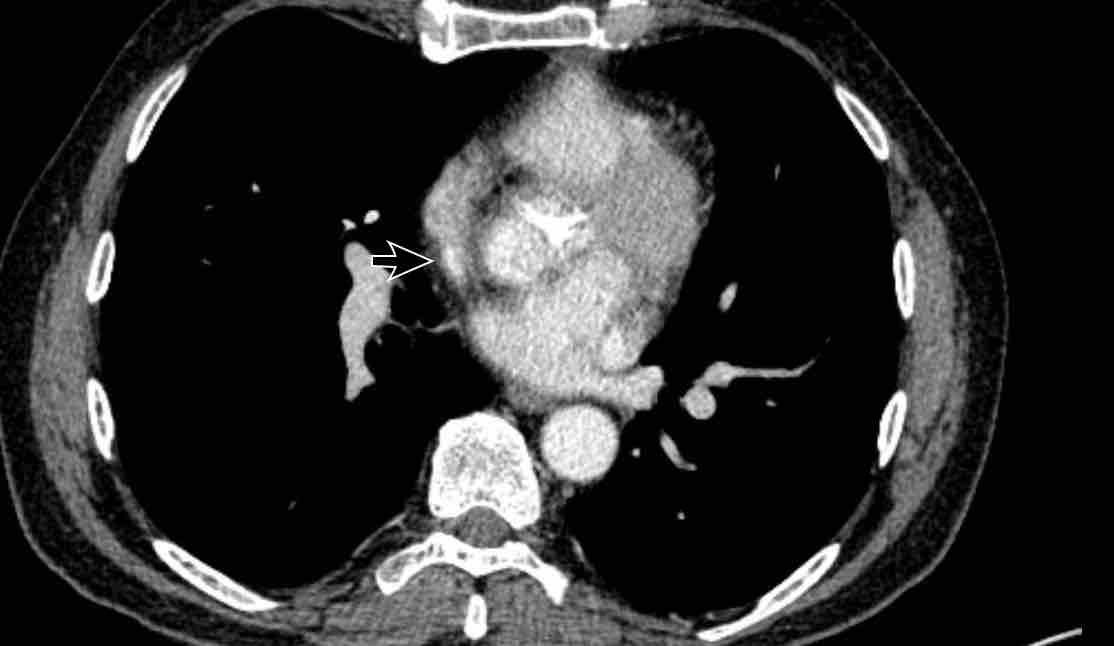

PAPVR bên trái phát hiện tình cờ với dẫn lưu trên tim của máu từ thùy trên trái vào tĩnh mạch tay đầu trái (các mũi tên).